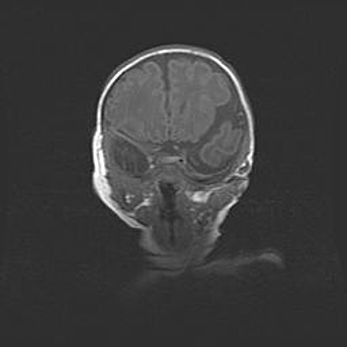

Церебральная ишемия II.

Возраст: 7 дней

Вес: 3350 г

Пол: женский

Окружность головы: 35 см

Срок гестации: 39 недель

Ишемия головного мозга – это состояние, которое развивается в ответ на кислородное голодание вследствие недостаточного мозгового кровообращения. У новорожденных она является следствием дефицита кислорода, что ведет к метаболическим расстройствам различной степени тяжести в тканях головного мозга, в том числе к развитию коагуляционных некрозов и гибели нейронов.